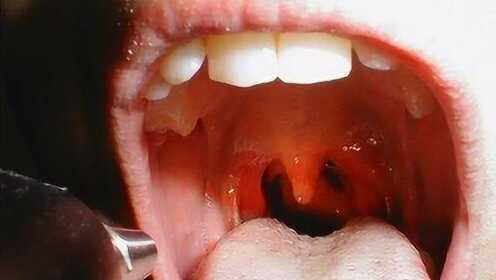

慢性咽炎概述

慢性咽炎是一種常見(jiàn)的喉部疾病,主要表現(xiàn)為咽部不適、干燥、瘙癢、疼痛等癥狀,由于長(zhǎng)期受到刺激或感染,咽部黏膜出現(xiàn)慢性炎癥表現(xiàn),慢性咽炎雖然不是嚴(yán)重疾病,但癥狀反復(fù)發(fā)作,嚴(yán)重影響患者的生活質(zhì)量。